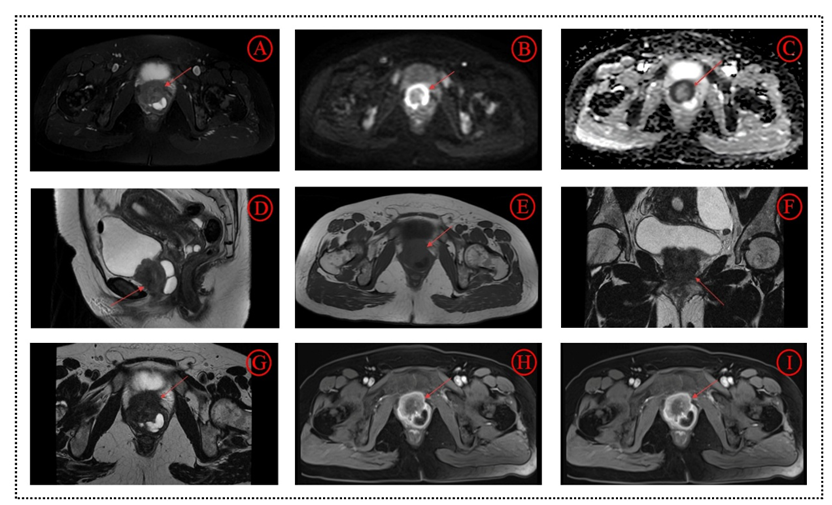

This case report presents a 43-year-old female with primary perineural neuroendocrine carcinoma (NEC) of the urethra, an exceptionally rare malignancy accounting for less than 0.5% of urinary tract tumours. The patient presented with dysuria and pain, initially misdiagnosed as a urinary tract infection. Imaging revealed a urethral mass with cystic changes posteriorly, showing heterogeneous enhancement with a characteristic “target sign” on MRI and restricted diffusion on DWI, correlating with high Ki-67 expression (70%). Histopathological and immunohistochemical findings confirmed large-cell neuroendocrine carcinoma. This case provides comprehensive CT and MRI imaging features aiding in early diagnosis and differential diagnosis from more common urethral carcinomas.